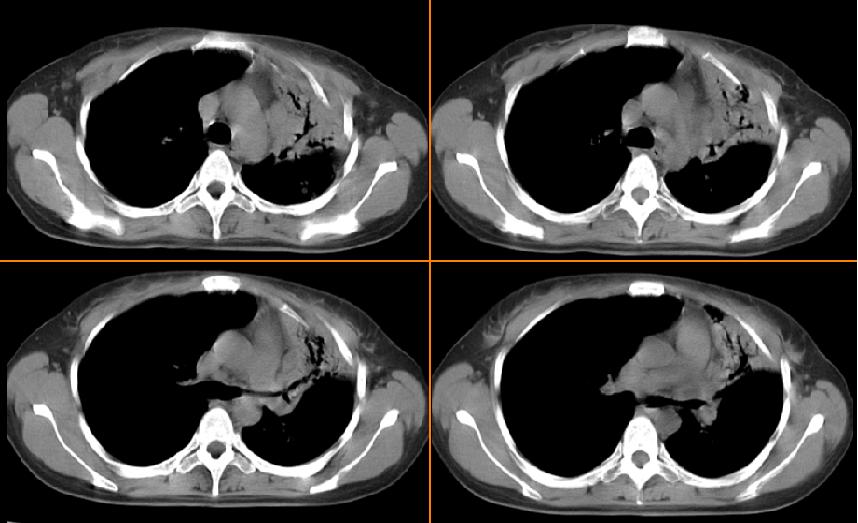

女,33岁,咳嗽5月。

双上肺tb.伴左上胸膜增厚粘连

考虑双肺上叶继发性肺结核伴左侧上胸壁胸膜肥厚 粘连。

左肺上叶前段致密,内见空气支气管征,相应部位胸膜增厚粘连,双肺上其他肺叶不同程度斑片状播散病灶,结合咳嗽5月的病史,考虑:双肺上叶继发性肺结核。

左肺上叶前段致密,内见空气支气管征,相应部位胸膜增厚粘连,双肺上其他肺叶不同程度斑片状播散病灶,结合咳嗽5月的病史,考虑:双肺上叶继发性肺结核伴左肺上叶肺含气不良。